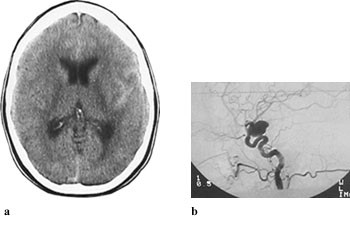

Opplysninger vedrørende cerebral angiografi forelå hos 64 av 70 pasienter med subaraknoidalblødning. Av disse hadde ti (16 %) normalt funn. Til sammen 63 aneurismer ble påvist hos 52 pasienter (81 %). Intracerebral arteriovenøs malformasjon ble påvist hos to pasienter. Hos seks pasienter ble det gjort samtidig funn av henholdsvis fire (n = 2), tre (n = 1) og to (n = 3) aneurismer ved samme undersøkelse. Aneurismer ble hyppigst påvist på a. cerebri media, a. communicans anterior og a. carotis interna (tab 2). Påvisning av blod i subaraknoidalrommet kunne gi indikasjon på lokalisering av aneurismet (tab 2, fig 2, fig 4). Prediksjon for påvisning av lokalisasjon av blødende aneurisme var kun meget god for aneurismer på a. cerebri media, hvor 12 av 13 aneurismer ble lokalisert korrekt. Det var dårligere prediksjon for aneurismer lokalisert til a. communicans anterior og a. carotis interna, med henholdsvis 11 av 18 og fire av ti aneurismer riktig lokalisert. Angiografi var utført hos åtte av ti pasienter med blod i septum pellucidum, og hos samtlige ble det påvist aneurisme på a. communicans anterior (fig 4). For de andre lokalisasjonene var det få observasjoner og lav treffsikkerhet.

Cerebral CT vil ofte kunne gi informasjon om lokalisering av aneurismet som ligger til grunn for blødning (8). Tidligere studier har vist at treffsikkerheten for lokalisering av aneurisme ut fra CT-undersøkelse kun var høy ved ruptur av aneurismer lokalisert til a. communicans anterior og a. cerebri anterior (15, 16). I vår studie fant vi høyest treffsikkerhet når det gjaldt blødning fra aneurisme på a. cerebri media, også med riktig sideangivelse, mens treffsikkerheten med hensyn til blødning fra aneurisme på a. communicans anterior var dårligere. Septum pellucidum-hematom er ansett som et sikkert tegn på aneurisme på a. communicans anterior (8), og dette ble bekreftet i vår studie. Derimot vil ikke alle aneurismer lokalisert til a. communicans anterior blø til septum pellucidum. Enkelte angir at blod i fissura interhemisphærica er et sikkert og hyppig tegn ved aneurismer på a. pericallosa, men dette var ukjent for oss da bildene ble gjennomgått. Lokalisering av blødende aneurisme før radiologisk eller kirurgisk sikring er spesielt viktig når det foreligger flere aneurismer. Multiple aneurismer, vanligvis to eller tre, kan finnes hos 20 – 30 % av pasienter med intrakraniale aneurismer (17). I akutte situasjoner kan det hende at pasientens tilstand ikke tillater den tidsbruk som går med til angiografi. En ”nødoperasjon” er helt avhengig av at CT viser og kan tolkes med størst mulig sikkerhet med hensyn til lokalisasjon.